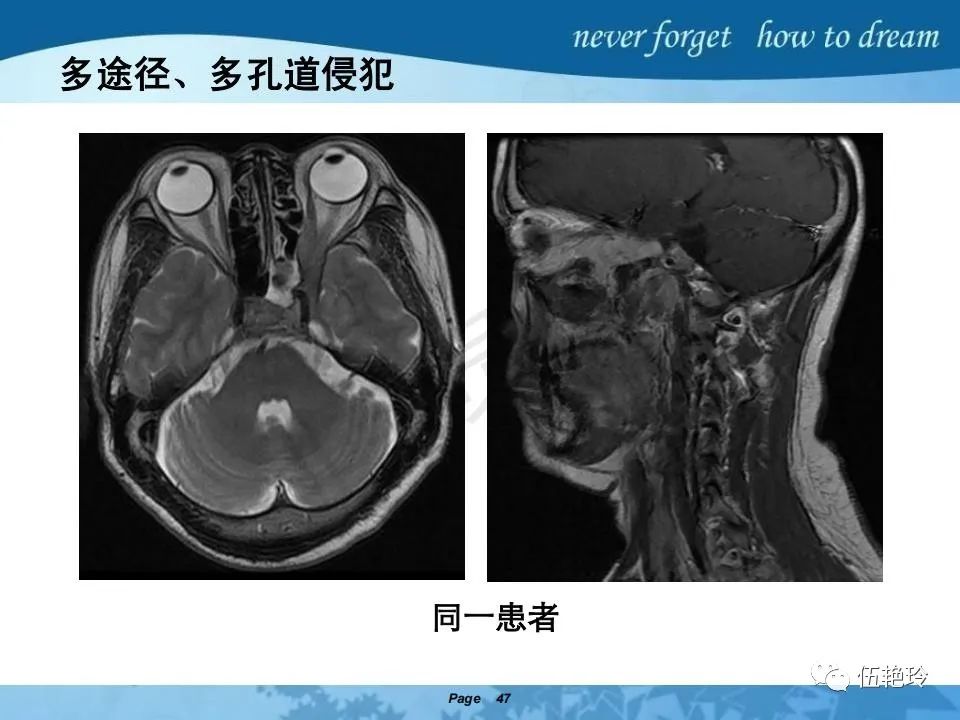

2.2 鼻咽特有的解剖途径:鼻咽癌原发灶循序进展的总途径:鼻腔(47.8%)→翼腭窝(15.2%)→ 眶下裂(3.2%)→眶尖(1.2%)→海绵窦(0.6%)。

2.31 向上颅内:①鼻咽顶壁→破裂孔(岩尖、斜坡)→蝶窦、海绵窦;②鼻咽顶壁→蝶骨基底部→蝶窦、海绵窦;③鼻咽侧壁→茎突前间隙→蝶骨大翼(卵圆孔)→海绵窦;④鼻咽侧壁→茎突前间隙→翼腭窝→ 颞下窝;⑤鼻咽前壁→鼻腔→翼突、翼腭窝→眶下裂→眶尖→海绵窦;⑥鼻咽前壁→鼻腔→上颌窦、筛窦;